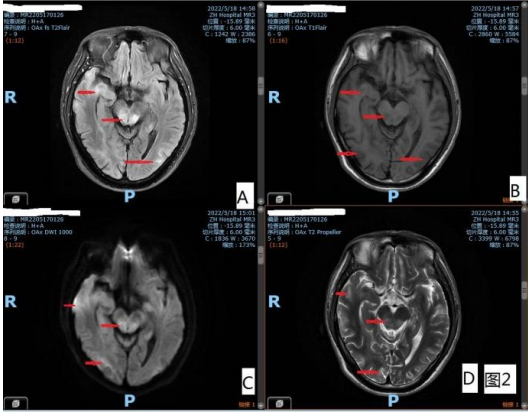

图 2 双侧中脑、颞叶、枕叶多发片状/斑片状 T1WI 稍低 /低信号,T2WI 高信号,T2-Flair 高信号,DWI 稍高信号 影 脑动脉 MRA 未见异常

颅脑 MRI:右侧顶叶、双侧颞叶、双侧枕叶、右侧岛 叶、右侧外囊、右侧丘脑、左侧海马、中脑、脑桥背侧可 见多发斑片状、片状 T1WI 低信号、T2WI 高信号、DWI 稍高信号,如图 1、图 2。